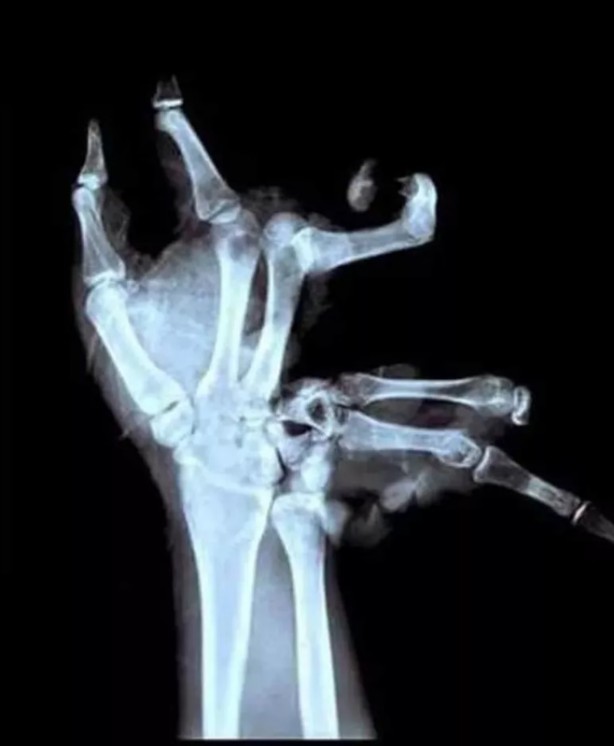

Hepsi birbirinden korkunç! Doktorları bile şaşkına çeviren görüntüler

İşte doktorları bile dehşete düşüren dünyanın en tuhaf röntgen filmleri...

Bıçakla parmağının bir kısmının kopmasına sebep olmuş bir hasta...